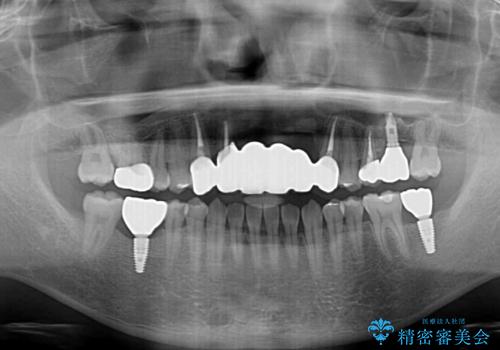

保存となった隣在歯も神経が失活していており、補綴治療が必要であったので、オールセラミッククラウンにて補綴治療することとしました。

奥歯には元々欠損があり、欠損に伴う咬合不正も認められたため、部分矯正を行った上でインプラント補綴治療も行うこととしました。